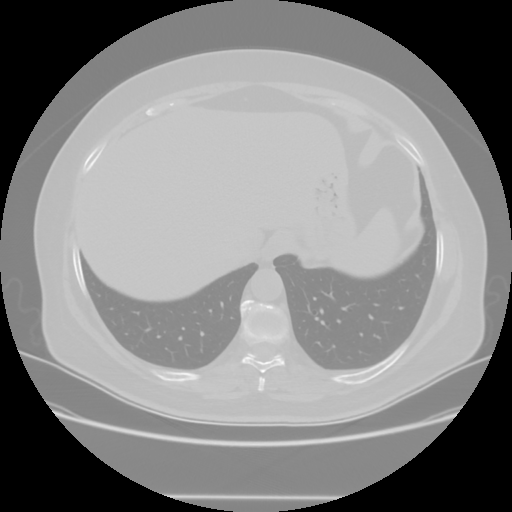

Targeted Slice 70 - Lung Window Analysis (Generated vs Real Venous)

0.782

Lung SSIM

70.6

Lung RMSE

32.3

Lung MAE

Average Lung Window Metrics Across All Slices (25 slices) - Generated vs Real Venous

0.771

Lung SSIM (Avg)

72.3

Lung RMSE (Avg)

34.1

Lung MAE (Avg)

Original NATIVE CT scan (input)

No window - Raw intensity values

Lung window (WL -600, WW 1500 β†’ Low βˆ’1350, High +150)